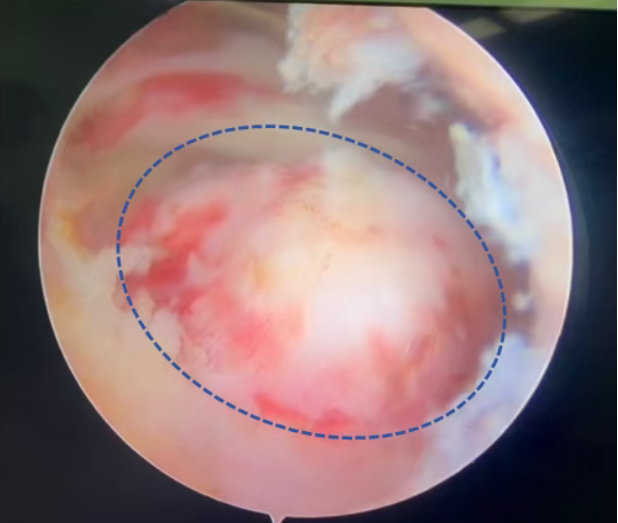

▲裸露的肱骨大结节及盂肱关节面(蓝色圈所示)